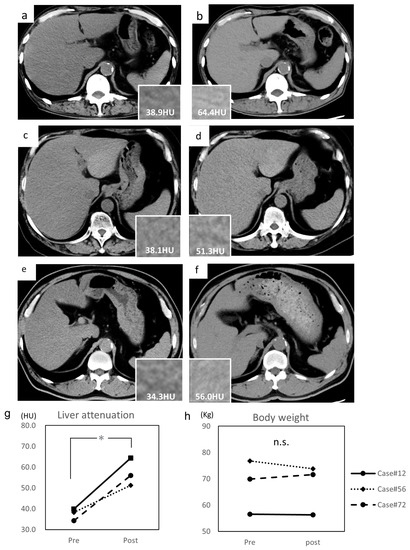

Among the 16 patients, three patients (Case #12, #56, and #72) who underwent an abdominal CT scan twice within at least a one-year interval were selected (Table 2).

The median interval was 95.1 (range, 67–118) weeks. The average pre-treatment liver attenuations of Case #12, #56, and #72 were 38.9 HU (Figure 3a), 38.1 HU (Figure 3c), and 34.3 HU (Figure 3e), respectively. The average post-treatment liver attenuations of Case #12, #56, and #72 were 64.4 HU (Figure 3b), 51.3 HU (Figure 3d), and 56.0 HU (Figure 3f), respectively. The average liver attenuation significantly increased after treatment (39.1 ± 1.2 to 57.8 ± 2.7 HU, p = 0.028) (Figure 3g). The L/S ratio also significantly improved (0.76 ± 0.04 to 1.18 ± 0.02, p = 0.012). Their TG levels decreased and LFT performance increased (AST, 30.3 ± 4.0 to 20.3 ± 3.1 U/L; ALT, 39.3 ± 4.1 to 20.0 ± 8.2 U/L; GGT, 43.3 ± 4.3 to 27.7 ± 5.2 U/L); however, LDL-cholesterol (135.3 ± 22.4 to 137.7 ± 26.7 mg/dL), HbA1c (8.1 ± 0.7 to 7.7 ± 0.5%), and body weight (67.7 ± 4.9 to 67.2 ± 4.5 kg) (Figure 3h) did not significantly differ.

Figure 3. Alteration of liver attenuation assessed by CT imaging. (a) Pre-treatment abdominal CT of Case #12, (b) post-treatment abdominal CT of Case #12, (c) pre-treatment abdominal CT of Case #56, (d) post-treatment abdominal CT of Case #56, (e) pre-treatment abdominal CT of Case #72, and (f) post-treatment abdominal CT of Case #72. (g) Alteration of liver attenuation assessed by CT imaging before and after treatment. Liver attenuations are indicated in each column. (h) Alteration of body weight before and after treatment. Hounsfield unit, HU. Data are expressed as mean with standard error of the mean (SEM). n.s. not significant, * p < 0.05.